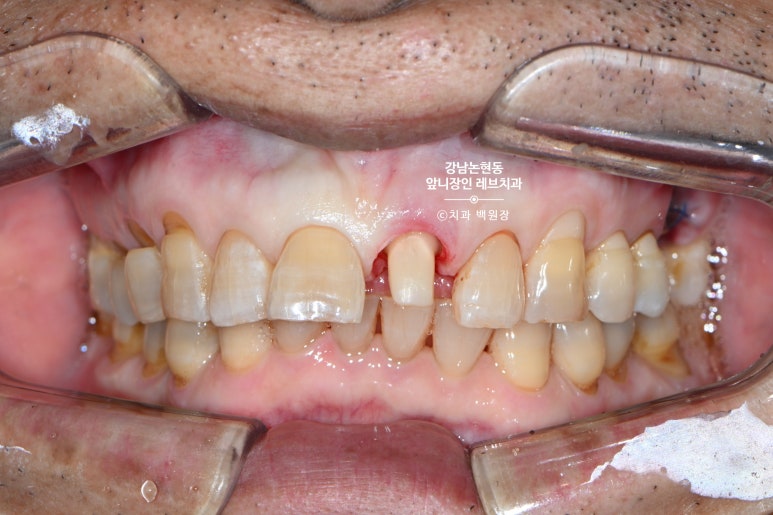

저희 논현동 레브치과의 자랑인 주성우 보철과 원장님이 아주 깔끔하게 치아를 다듬어 주셨습니다.

거의 무에서 유를 창조한 셈인데요.. 저 남아있는 치아 안에 굵직한 기둥이 심겨져 있습니다.

잘 보시면 뿌리쪽에 약간 어두운 치아가 있는데, 그것이 본래 갖고 계신 자기 치아이고,

보다 밝은 색으로 대부분을 이루고 있는 부분이 기둥 (fiber post) + 레진 코어 (resin core) 입니다.

그리고 많이 티는 안나지만, 대칭되는 가운데 앞니와 최대한 비슷하게 만들기 위해 잇몸 경계도 성형해줍니다.